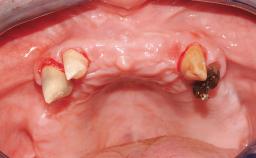

Immediate Loading of Six Implants in the Mandible and Six Implants in the Maxilla and Final Restoration with Full-Arch CAD/CAM Metal Framework FDPs Involving Digital Planning and Guided Surgery

Immediate loading of dental implants is increasingly popular with clinicians and patients. The idea of delivering a restoration directly after implant insertion,combined with a less invasive procedure (flapless protocol), has made treatment protocols involving dental implants more accessible to dentists and patients. However,immediate-loading concepts require sophisticated and exact planning. To facilitate this, conventional panoramic tomographs and periapical radiographs are often taken with the patient wearing a radiographic template simulating the preoperative prosthetic design. However, these radiographs do not provide all the necessary information. In addition, some protocols call for conventional surgical templates fabricated on the diagnostic cast. These will inform the bone drilling points and drill angles, but do not reference the underlying anatomical structures or provide exact 3-D guidance.

Case Type Edentulous Maxilla

Defining Characteristics Fully edentulous upper jaw to be rehabilitated with four or more implants